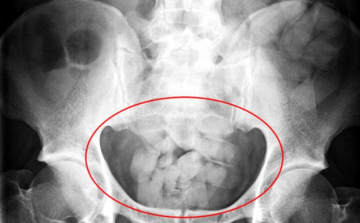

Kokainnal a gyomrában érkezett egy nő a ferihegyi reptérre

Mintegy 13 millió forint értékű kokainnal a gyomrában próbált meg bejutni az országba egy venezuelai nő, akit a NAV pénzügyőrei feltartóztattak a Liszt Ferenc-repülőtéren - közölte a NAV hétfőn az MTI-vel.